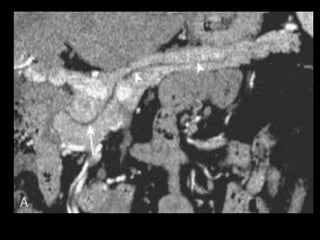

Todo o ducto pancreático pode ser visualizado num

único plano com as reformatações curvas produzidas

com os aparelhos de TCMD.